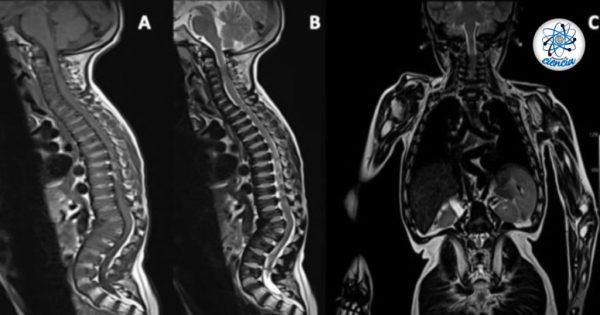

Comparte esta información en tus redes socialesCrédito de imagen: ScienceDirect. ¿Has escuchado hablar sobre el Síndrome de Morquio? ¿Sabes de...